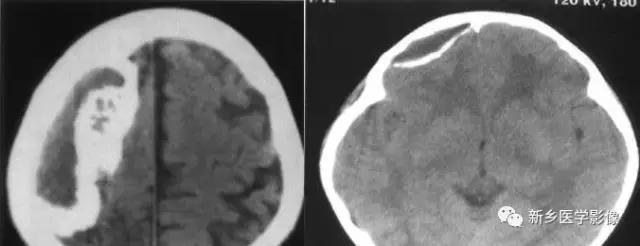

十八、脑三叉神经血管瘤病

又称颅颜面血管瘤病,Sturge-Weber综合征,绝大多数为散发。

CT:①钙化灶多为单侧性,始于枕叶,逐渐向前发展,居脑表浅部位,沿脑回呈曲线形或宽大锯齿状钙化;

②脑组织异常:局部脑组织坏死、胶质增生、钙化(斑点状、锯齿状),脑萎缩,脑皮质萎缩以枕叶萎缩明显,亦可累及整个大脑半球,脑沟增宽,但脑室不扩大;

③患侧颅骨增厚,头颅不对称;

④软脑膜血管畸形,增强扫描可见脑回状强化;脑深部异常引流经脉;

⑤75%病例同侧脉络丛增大,且显著强化。